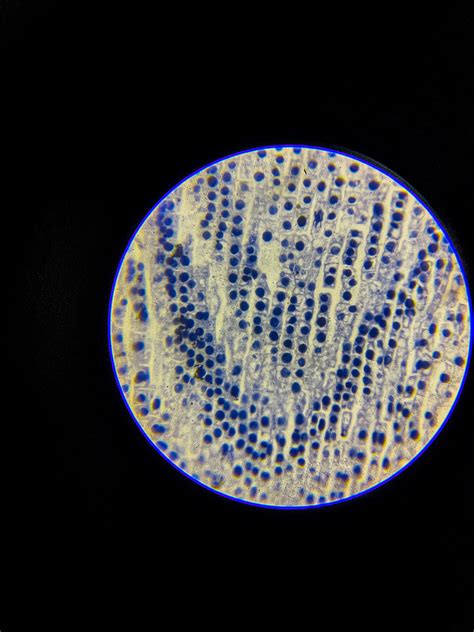

Food Allergies - Dr. Ankit Parakh